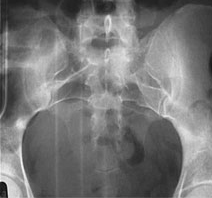

• X-ray and fluoroscopy. X-ray, the most common form of diagnostic imaging, uses a low dose of radiation to diagnose problems. Fluoroscopy is a live X-ray technique used to observe both the structure and function of organs in real time.